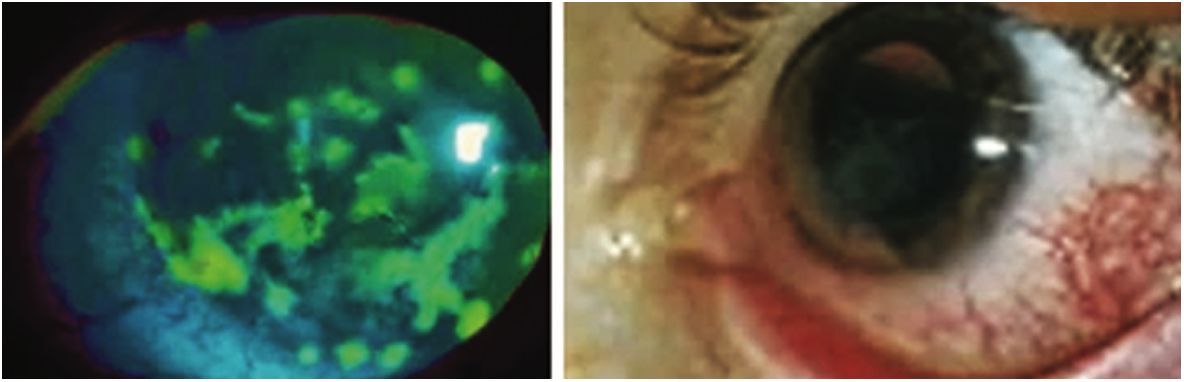

Тиаскопия – осмотр роговицы, подкрашенной раствором флюоресцеина натрия, в поляризованном свете (рис. 17).

Рис. 17. Дефекты в эпителии роговицы, выявленные методом тиаскопии при синдроме сухого глаза

Fig. 17. Defects in the corneal epithelium detected by thiascopy in dry eye syndrome

Исследование выполняют на щелевой лампе, оснащённой синим светофильтром. Тест оценивается как положительный при обнаружении в эпителии роговицы точечных дефектов (рис. 18).